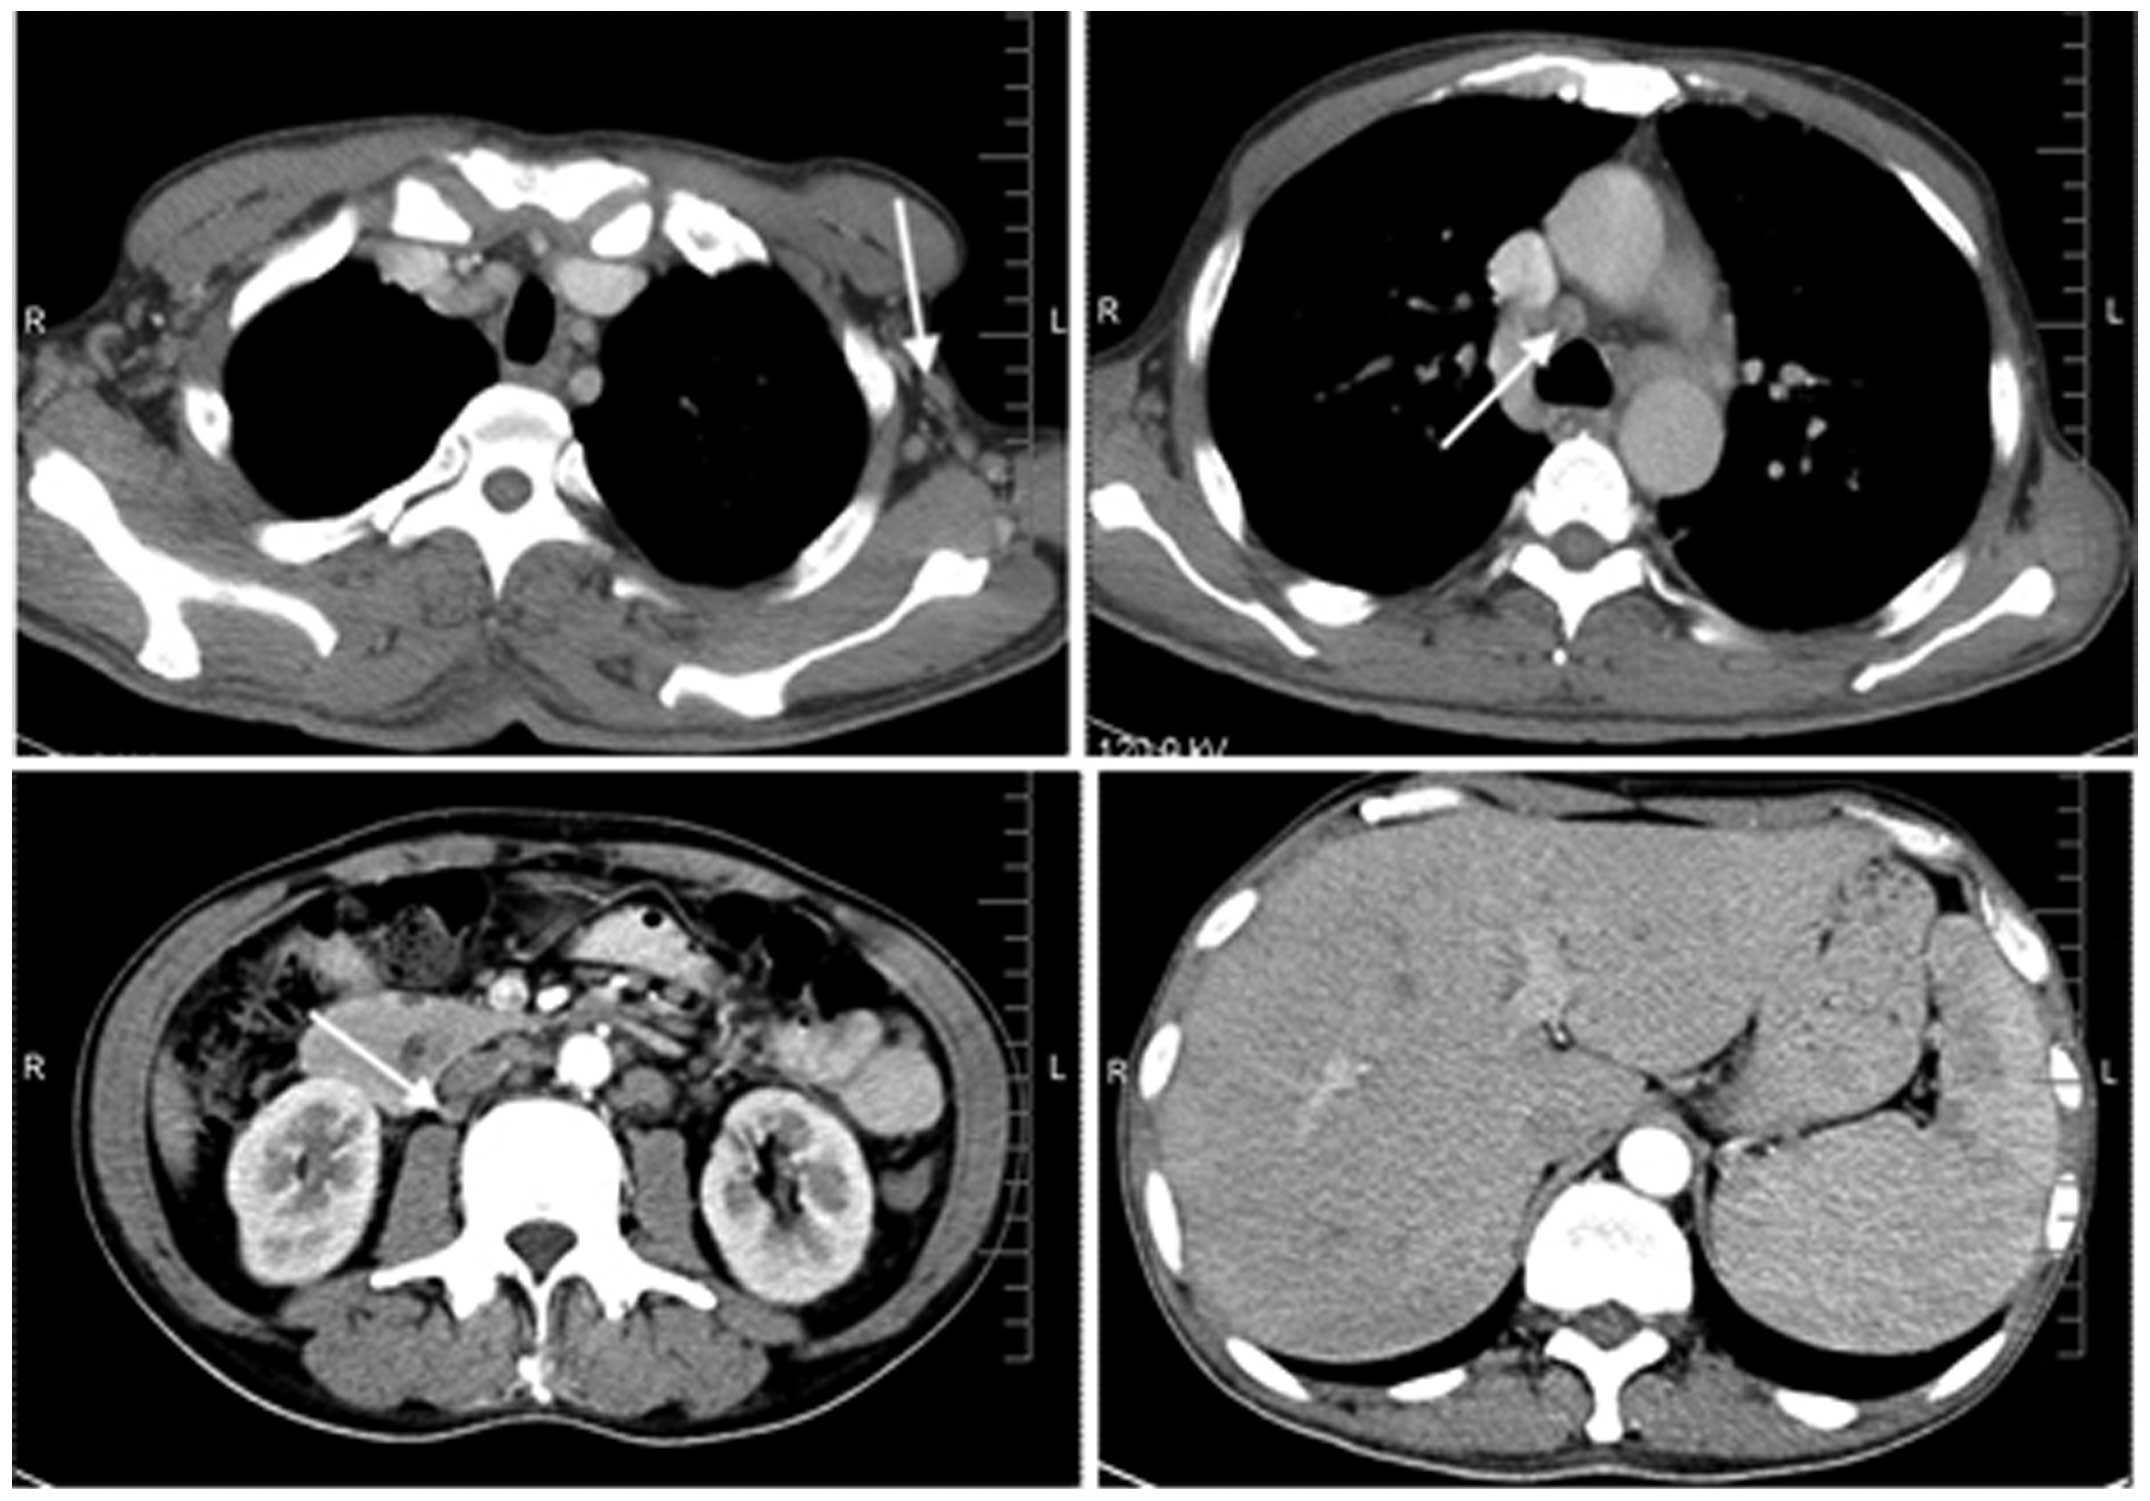

A 53-year-old male developed weakness of the lower limbs, numbness and stabbing pains below the ankle and wrist joints, accompanied by a low fever and night sweating. One month later, the patient developed a red, full-body rash and noticed gradually worsening instability when walking. A rapidly proliferative painless lymph node on the left side of the neck was also noted. As a consequence, the patient was admitted to the Xiangya Second Hospital of Center South University (Changsha, Hunan, China). A physical examination revealed lower limb paresis (grade 4/5 according to the manual muscle testing) (3), a high fever, a red rash and swelling of the left neck lymph nodes to a size of 2.0×1.5 cm2. Blood analysis revealed the following results: White blood cell count, 14.6×109/l (normal range, 3.0–10.0×109/l) [87.6% neutrophils (normal range, 50–70%) and 5.6% lymphocytes (normal range, 20–40%)]; hemoglobin, 88 g/l (normal range, 20–160 g/l); platelet count, 462×109/l (normal range, 100–300×109/l); sodium, 133 mmol/l (normal range, 136–146 mmol/l); calcium, 1.96 mmol/l (normal range, 2.08–2.80 mmol/l); albumin, 22.8 g/l (normal range, 35–50 g/l); lactate dehydrogenase, 290 IU/l (normal range, 100–300 IU/l); rheumatoid factors, 23.7 IU/ml (normal range, 0.0–20.0 IU/l); erythrocyte sedimentation rate, 65 mm/h (normal range, 0–15 mm/h); and C-reactive protein, 15 mg/dl (normal range, 0–10 mg/dl). Endocrine investigations revealed reduced levels of neo-hombreol F (130 ng/dl; normal range, 250–836 ng/dl). The serum immunoglobulin (Ig)G (31.5 g/l), IgA (8.55 g/l) and IgM (3.12 g/l) levels were all high (normal ranges, 7.6–166 g/l, 0.71–3.35 g/l and 0.48–2.12 g/l, respectively), and immunoelectrophoresis revealed monoclonal gammopathy (γ globulin, 51.5 g/l; normal range, 20.0–30.0 g/l). Bence-Jones protein was not detected in the urine. The electromyography test showed a motor-dominant polyneuropathy with demyelinating features in the lower limbs. An ultrasonic cardiogram revealed that the interventricular septal and left ventricular posterior walls were thickened. A biopsy of the left neck lymph nodes revealed that the normal architecture was lost, except for the presence of occasional depleted follicles with concentrically arranged follicular dendritic cells, and that the architecture was effaced by polymorphic infiltrate with marked vascular proliferation (Fig. 1). Immunohistochemistry revealed the following results: CD21 (++), CD3 (+), CD4 (+), CD45RO (++), CD8 (+), Ki-67 (++; 60%), CD79a (−), anaplastic lymphoma kinase (−) and CD20 (−). The staining scores were defined as follows: −, negative (<3% cells positively stained); +, weakly positive (3–24% cells positively stained); ++, moderately positive (25–49% cells positively stained); +++, strongly positive (≥50% cells positively stained). Computed tomography scans (Fig. 2) revealed swelling of the axillary, mediastinal and retroperitoneal lymph nodes, and hepatosplenomegaly. Magnetic resonance imaging of the head was normal. Abnormal cells were confirmed by bone marrow punctures. These findings were consistent with a diagnosis of stage IV AITL, according to the World Health Organization classification (4). The patient was also diagnosed with POEMS syndrome, as determined by the criteria defined by Dispenzieri et al (5). Following two courses of gemcitabine (1,600 mg, days 1 and 8), oxaliplatin (150 mg, day 1), DXM (10 mg, days 1–5) and L-asparaginasum (1,000 IU, days 1–5) therapy, in a 21-day cycle, the lymphadenopathy was reduced, and the skin changes and limb neurological symptoms improved markedly.

Figure 2

Computed tomography scans revealing swelling of the axillary (top left image), mediastinal (top right image) and retroperitoneal (bottom left image) lymph nodes, and hepatosplenomegaly (bottom right image). Arrows indicate the areas of swelling.